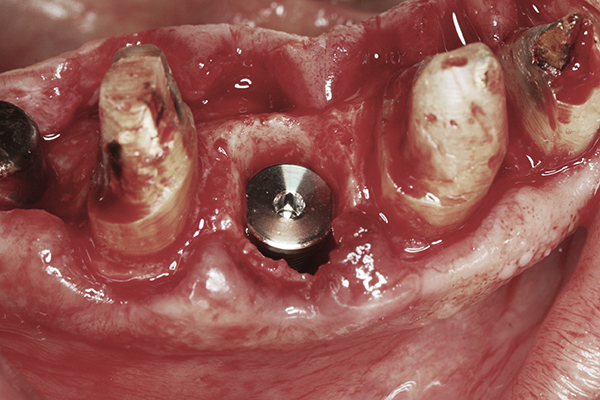

Apparently with time, stable implants placed with low initial torque develop bone characteristics around them that are similar to sites where implants were placed with a high initial torque (Figure 4 and Figure 5). Conversely, for implants placed with a high initial torque, the healing process, despite the high initial torque, provides a level of biologic stability that is not necessarily influenced by the initial insertion torque value.

Fig 4. Clinical view of an implant placed into an immediate extraction socket at site No. 28. A n insertion torque of <10 Ncm resulted in a spinner.

Figure 4

Fig 5. Radiograph of the implant at site No. 28 (shown in Figure 4) with an oversized cover screw, which was used to assist in stabilizing the implant within the osteotomy.

Figure 5